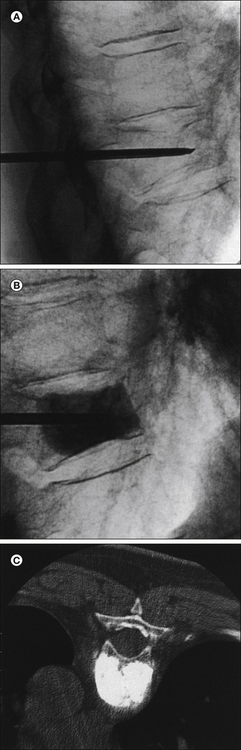

Figure 71-1 Vertebroplasty.

A, Thoracic compression fracture with a transpedicular needle in the vertebral body. B, Injection of methacrylate into the vertebral body as seen under fluoroscopy. C, The finished product on axial computed tomography after bilateral transpedicular injection. The vertebral body is now filled with methacrylate and strength is restored. Pain relief was immediate.